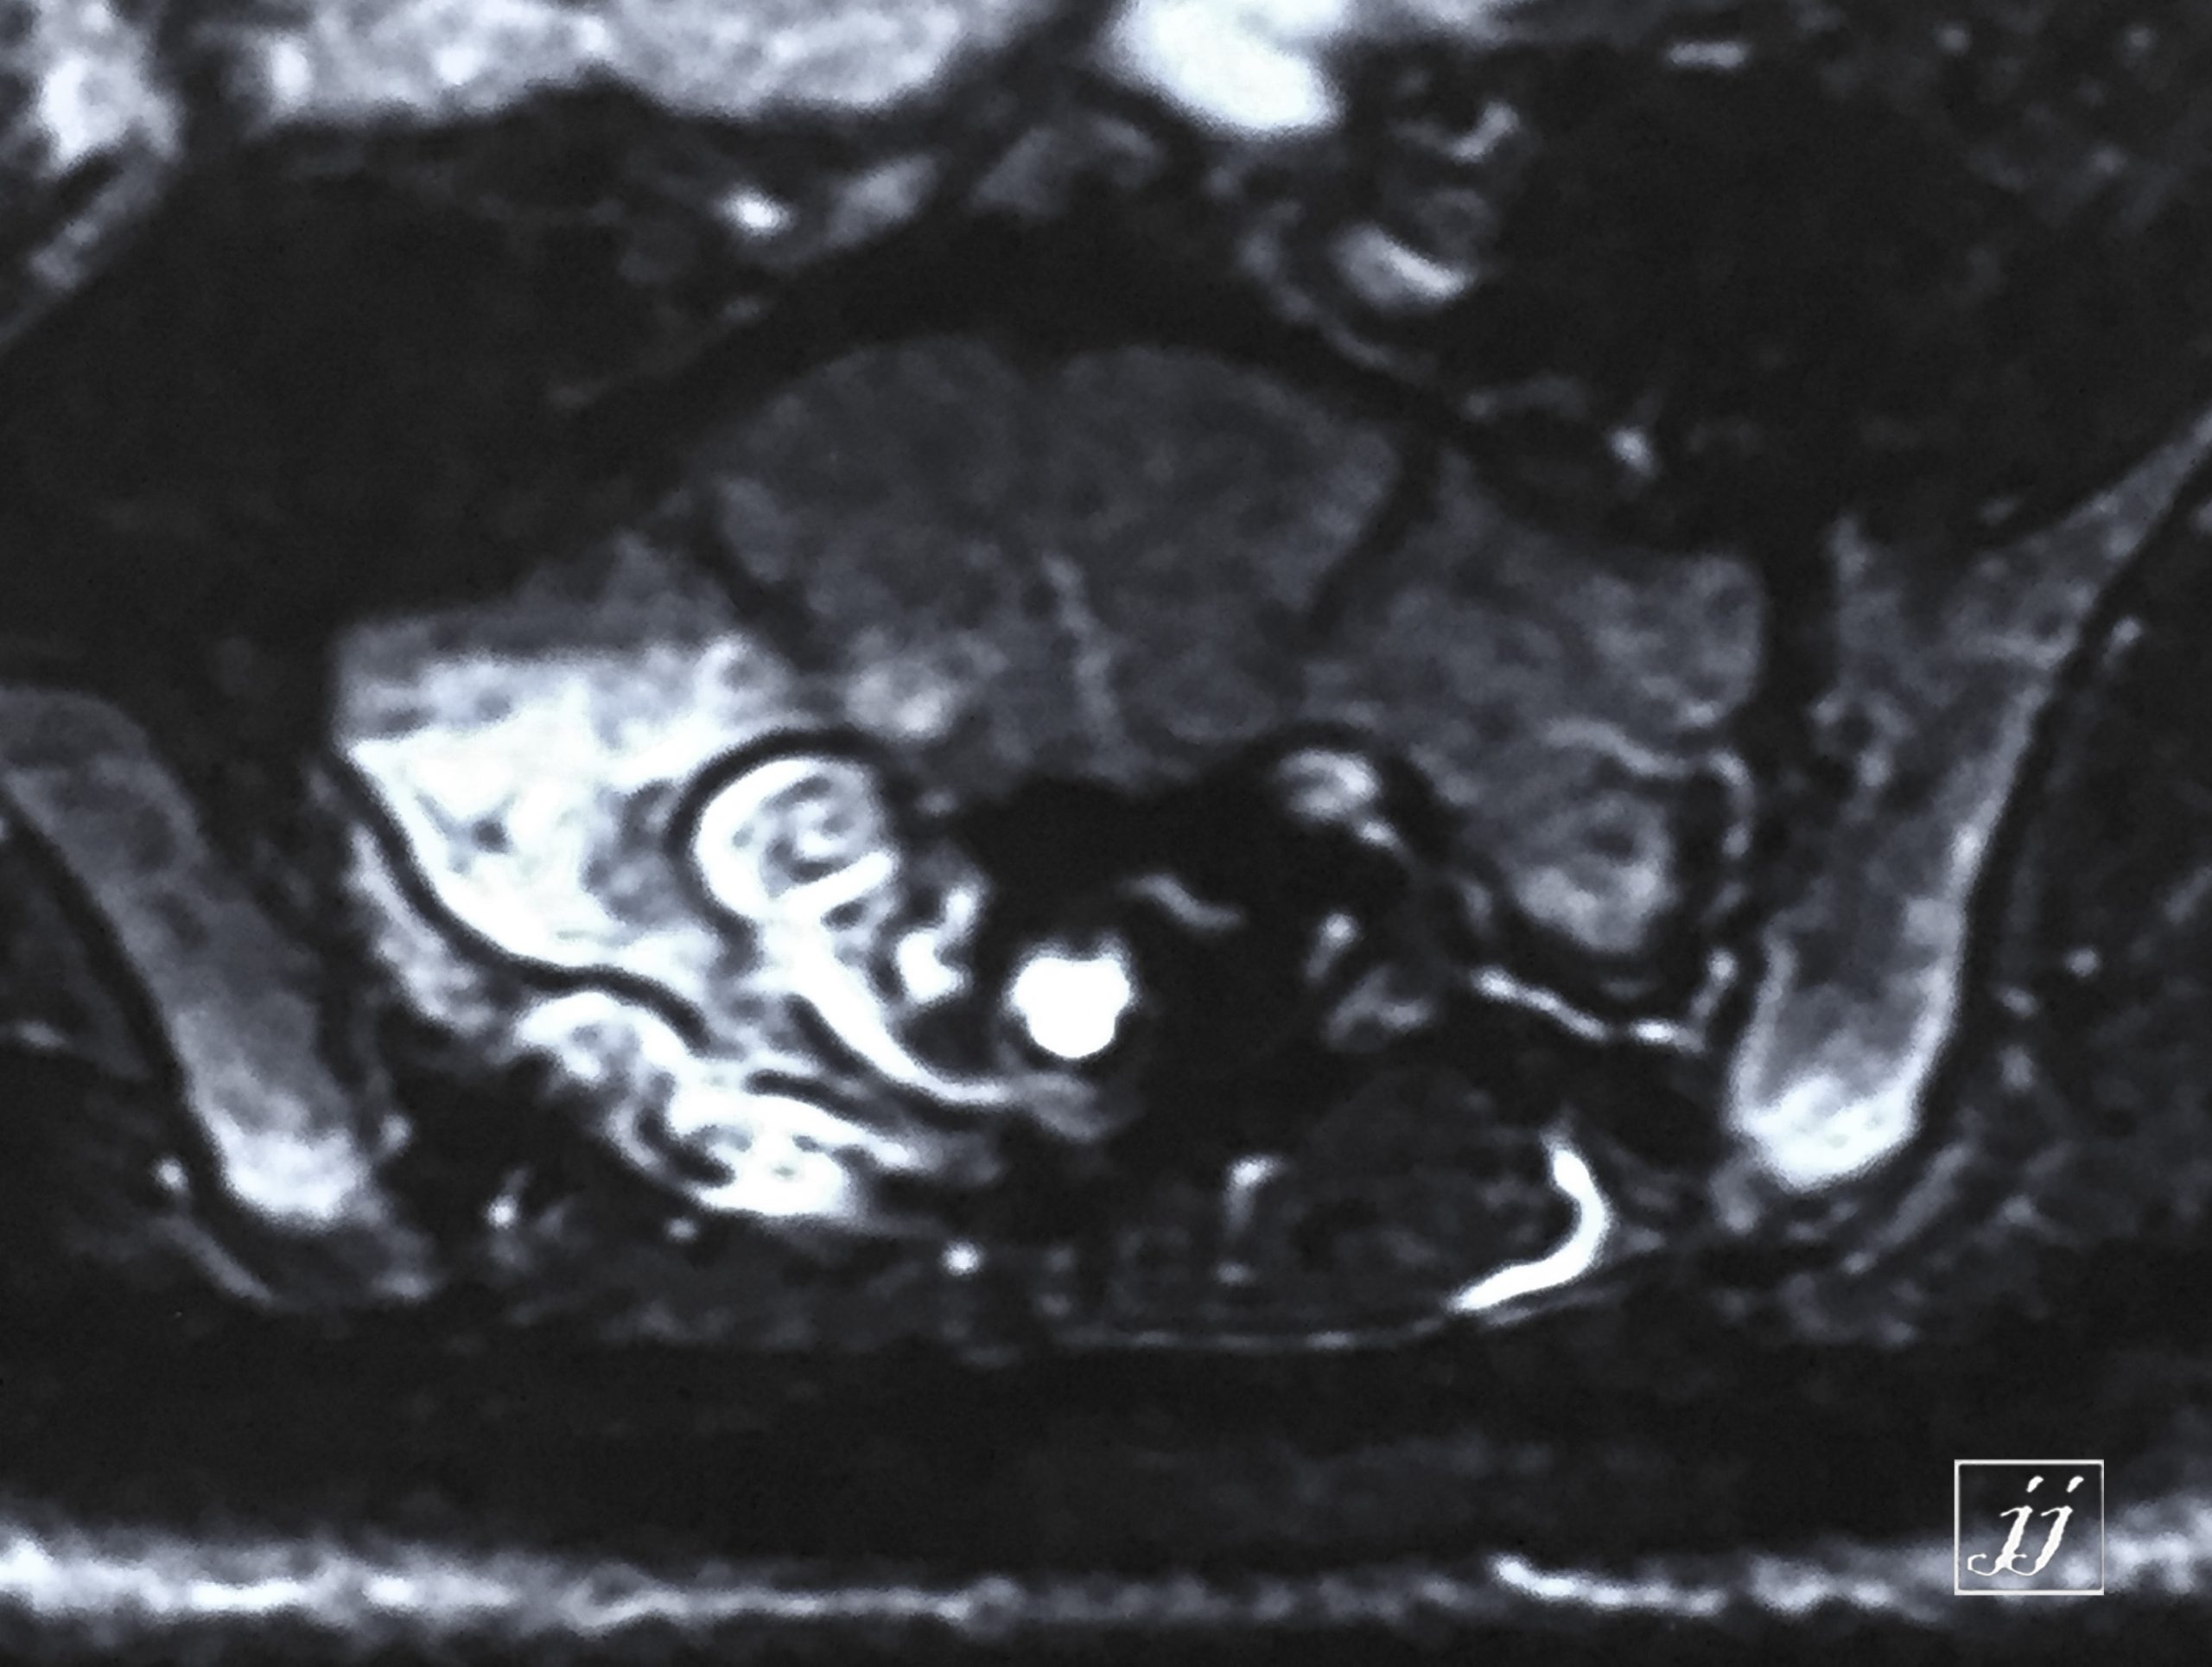

Spine- primary fusion of L54 L5 (11)